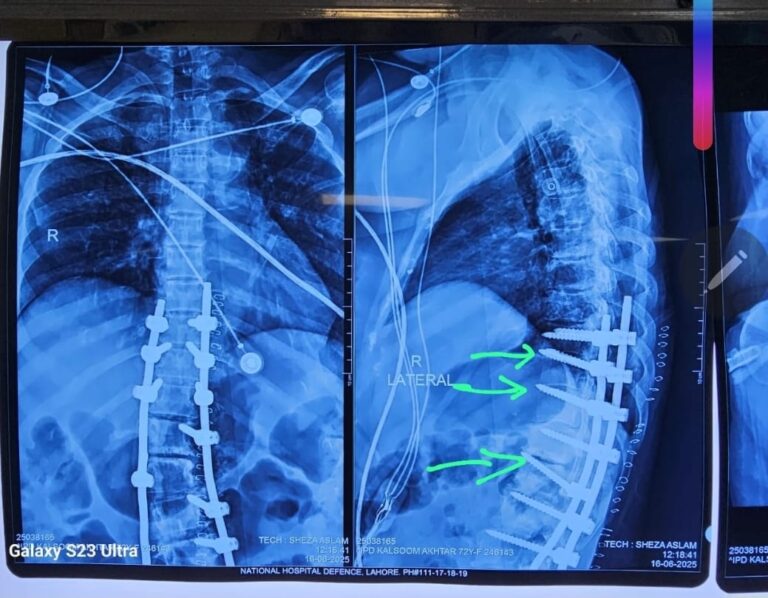

We are pleased to share that a complex spine surgery was successfully completed. During the procedur…